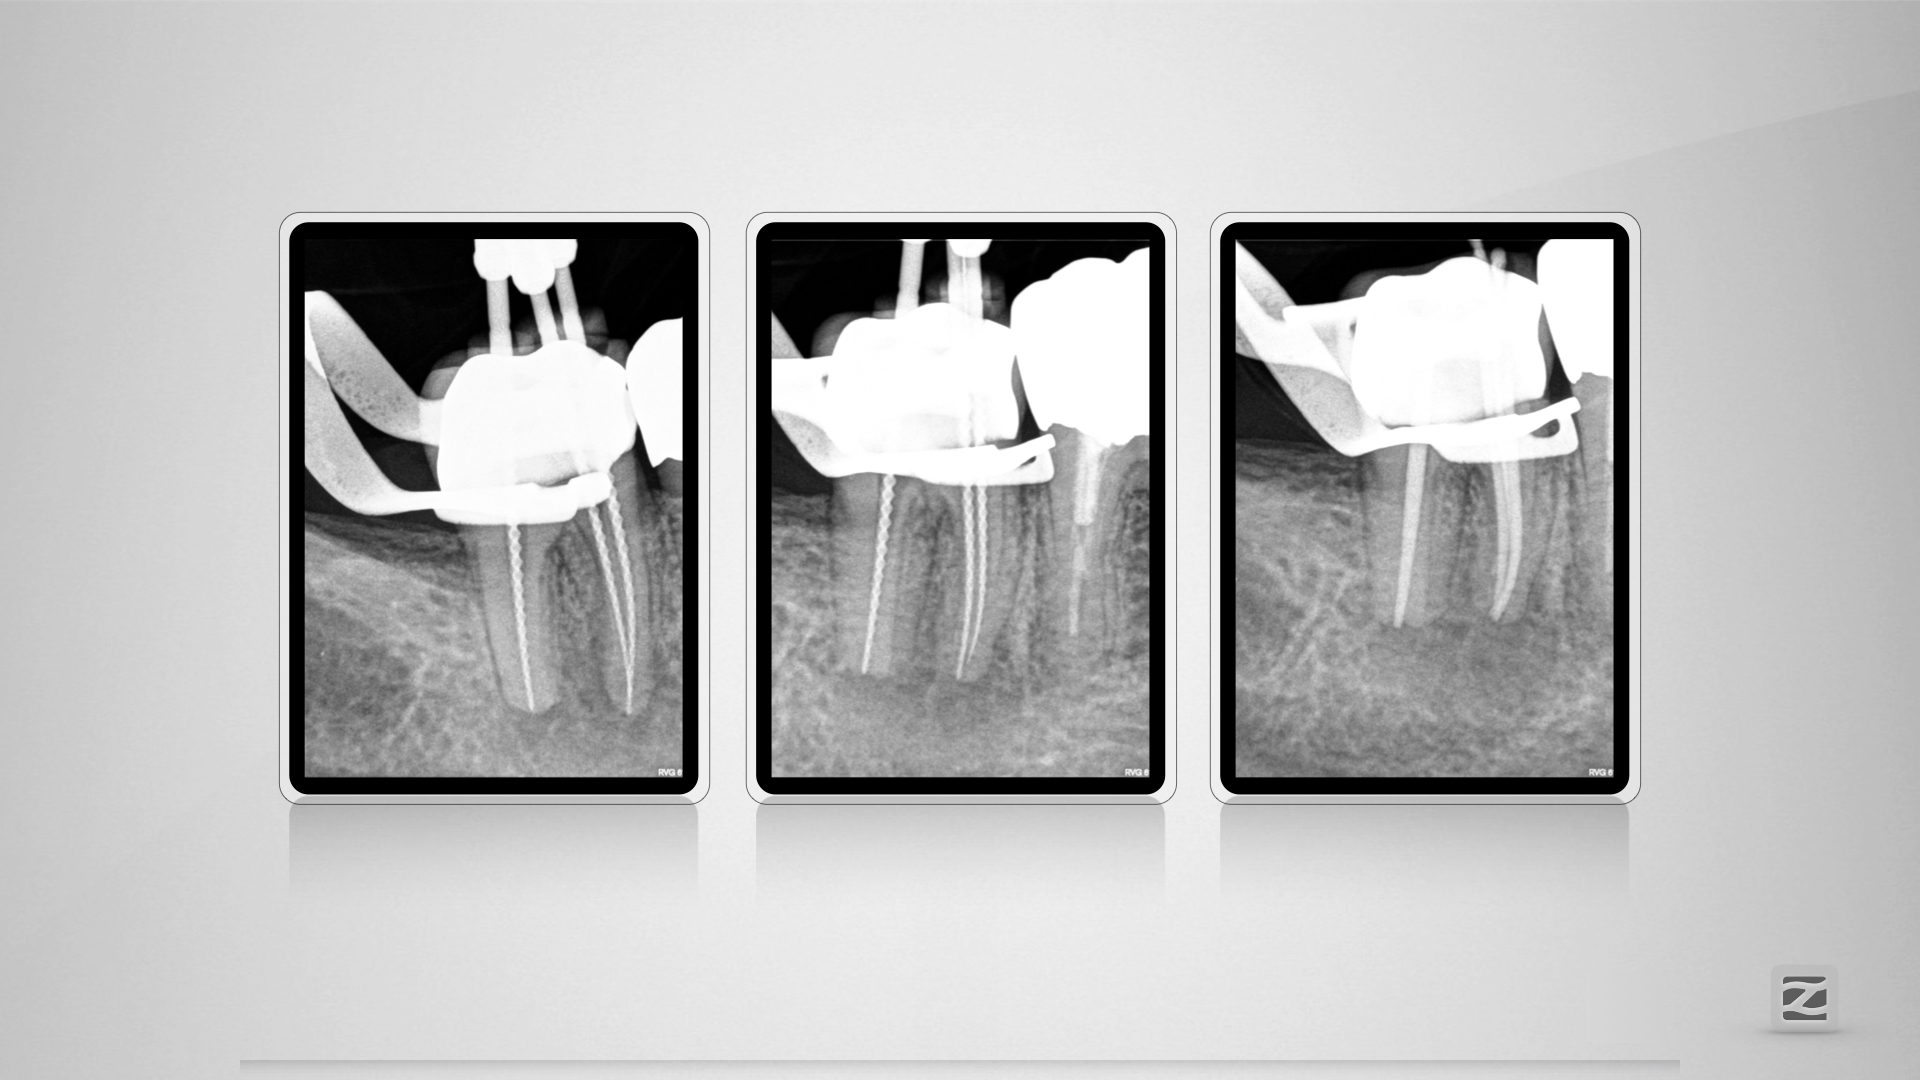

47D.010

Kuhfuß